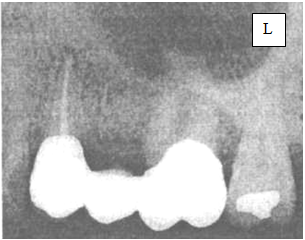

4.Назовите снимок, опишите 2.4 зуб.

4. Название внутриротовая рентгенограмма зубов 2.4, 2.6, 2.7

в общем, с описанием зуба 2.4 всё понятно, но: правильно ли я вижу, что в области корня зуба 2.4 имеется очаг деструкции костной ткани, округлой формы, с четкими границами, размером примерно 5-6 мм, и ВОЗМОЖНО, ЭТО РЕНТГЕНОЛОГИЧЕСКОЕ ПРОЯВЛЕНИЕ АКТИНОМИКОЗА!